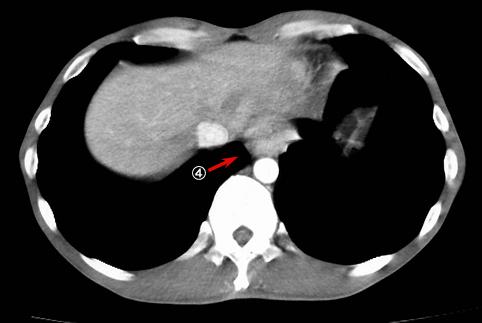

다발성의 벽내 전이병변을 동반한 궤양침윤형의 진행위암

악성 상피성종양/인환세포암

식도/하

CT

20~24